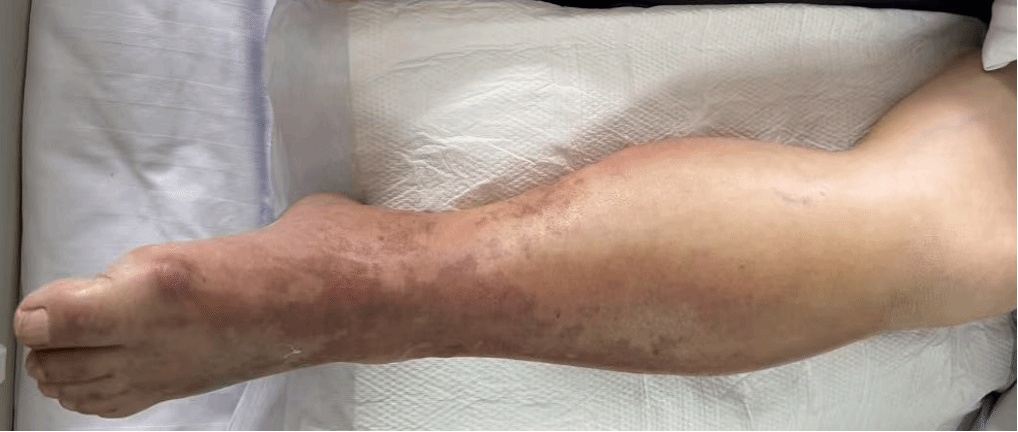

术前肢端末梢青紫、皮温冰冷、无动脉搏动

术后患肢肿胀明显、出现张力性水泡,动脉搏动良好,皮温稍低

患者出院时患肢已基本恢复,动脉搏动良好、皮温正常